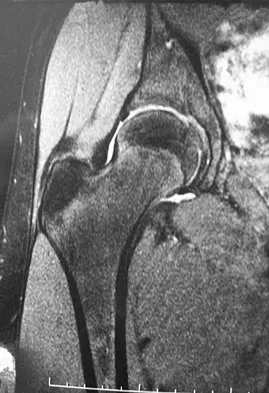

A 21-year-old collegiate female cross-country athlete reports right hip pain that begins about 12 miles into a run, followed by pain resolution when she discontinues running. However, each time she tries to resume a running program, she experiences recurrence of pain deep in the anterior groin. A plain radiograph and MRI scan are shown in Figures 8a and 8b. Management should consist of

Explanation

The history is consistent with a stress fracture. Findings on the plain radiograph are marginal, but the MRI scan shows evidence of stress reaction in the medial neck of the femur (compression side). A lesion on the compression side is not normally at risk for displacement and usually can be managed nonsurgically. A bone scan would further identify the lesion but is not necessary. A skeletal survey and chest radiograph are used in staging a tumor. Radioisotope injection and guided biopsy are sometimes used for osteoid osteomas. Boden BP, Osbahr DC: High-risk stress fractures: Evaluation and treatment. J Am Acad Orthop Surg 2000;8:344-353.